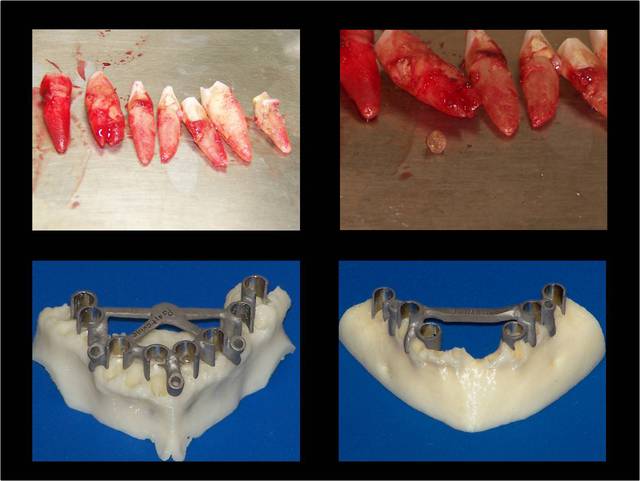

La vidéo présente à partir des plans de traitements, des chirurgies de beotien , des dispositifs médicaux sur mesure positdental et positguide la mise en charge immédiate post-extractionnelle d’un bridge provisoire à armature métal en prothèse fixe sur implants cône morse donc sans vis de maintien. Une question est émise « comment obtient-on ce résultat ? ». Une partie des réponses comme la prédictibilité, la reproductibilité peuvent y être déduite pour d’autre il faudra la bonté de beotien de faire partager les résultats clinique.il nous fait la générosité de poster la phase cicatriciel à 7 jours et des photos de la chirurgie sur un cas.

planif cas 1